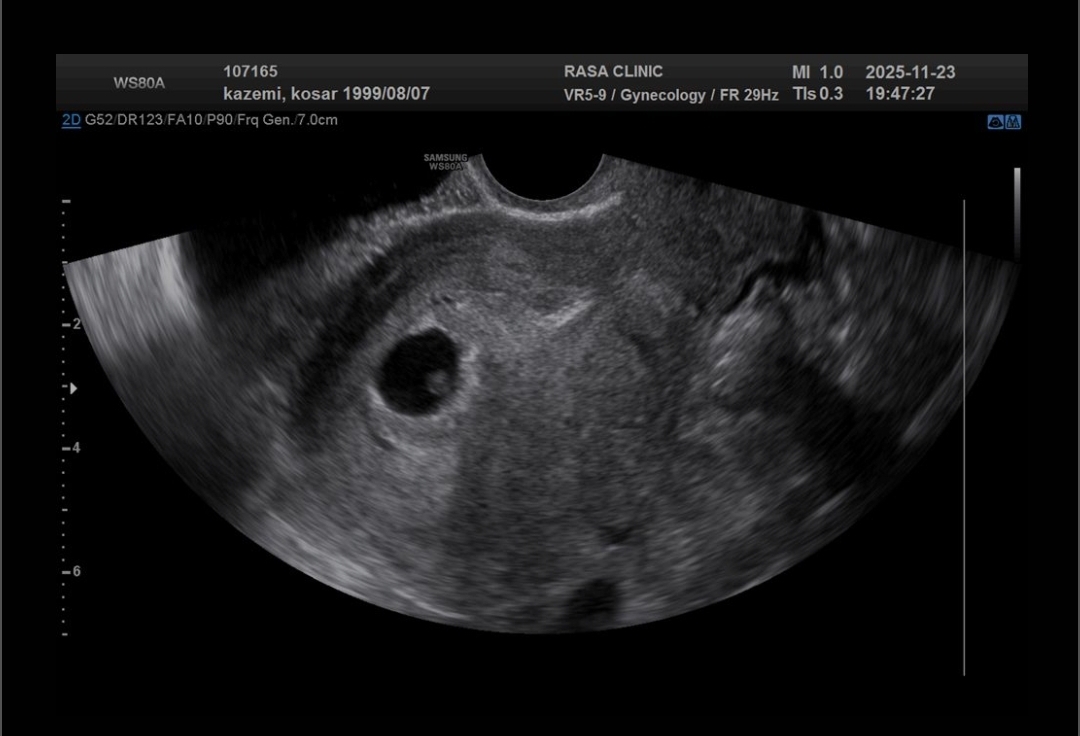

امروز برای چک کردن ساک بارداری رفتم سونو ک دیدم قلبشم تشکیل شده میشه چک کنید لطفا مشکلی نداشته باشه❤️🙏

ساک بارداری ب این گردی من ندیده بودم تاحالا😂😍

سونو قلب ۶ هفته

پزشک اوما

مبارکتان باشد همه چیز عالی است ، بله یک ساک بارداری خوشگل هست یک گردو کوچولوی دلبر درراه دارید ❤️😘😊